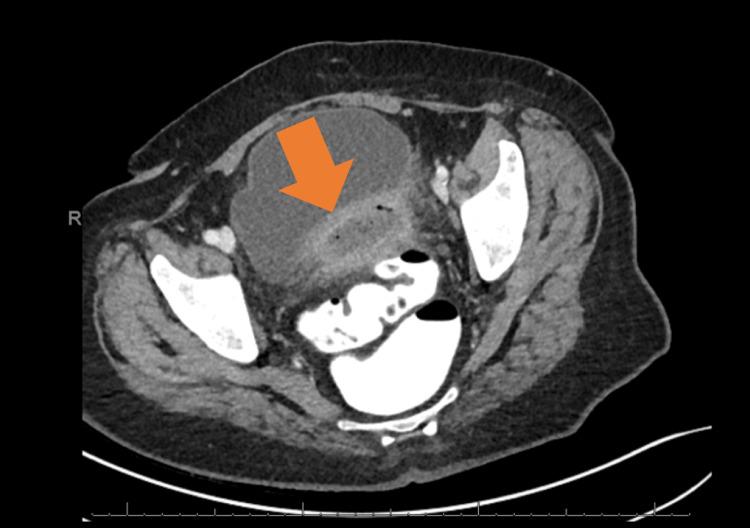

Neutrophilic dermatosis (ND) is a category of diseases characterized by trauma-induced, autoinflammatory cutaneous eruption. Comorbid systemic disease is common with a predilection for malignancy, inflammatory bowel disease, and rheumatologic disease. Rarely, it can manifest with aseptic shock, an entity referred to as necrotizing neutrophilic dermatosis (NND). NND may occur in the postoperative setting and is often misdiagnosed as a necrotizing soft tissue infection. Unfortunately, the treatment for a necrotizing soft tissue infection, namely, wide debridement, is often detrimental in the setting of NND. We present the case of a woman with underlying myelodysplastic syndrome who developed episodic postoperative hemodynamic collapse followed by delayed necrotic peristomal ulceration following colonic diversion for complicated diverticulitis. Infectious workup and operative re-exploration were unrevealing. Pathologic assessment of affected skin tissue showed changes consistent with ND, ultimately leading to the diagnosis of NND. Her clinical course dramatically improved with the initiation of immunosuppressive therapy. The mimicry of NND to a potentially lethal necrotizing soft-tissue infection creates a grave diagnostic dilemma in the postoperative period. A general lack of knowledge of NND among non-dermatologic specialists produces an opportunity for misdiagnosis and inappropriate surgical interventions, namely, serial debridement. Several clinical cues may aid in the earlier recognition of NND. The cornerstone of treatment involves systemic corticosteroid therapy with adjunctive therapy for refractory cases. NND must be considered in the differential diagnosis of necrotizing soft tissue infection as early recognition may result in the avoidance of deleterious surgical interventions.